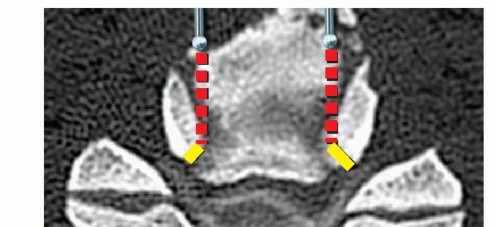

### TECH FIG 1 • Limits of corpectomy. A. The width of the corpectomy is based on that necessary to decompress the spinal cord and can be estimated on preoperative imaging. B. In general, a corpectomy spanning from the medial border of one uncinate to the other will be sufficient at the vertebral body level. (continued) The width of the corpectomy required to decompress the cord should be based on preoperative imaging studies (TECH FIG 1). Generally, sufficient decompression will occur if the width of the decompression spans from uncinate to uncinate. Wider decompressions beyond the medial border to the uncinates are typically performed at the disc level, where a combination of cord and root compression may occur, but are not necessary at the vertebral body level, where only the spinal cord is compressed.

TECH FIG 1 • (continued) C. At the level of the disc space, a wider decompression may be necessary for satisfactory root decompression (yellow lines). Staying within the uncinates will allow for thorough decompression while avoiding vertebral artery injury, unless a vertebral artery anomaly exists. Such anomalies are more likely to occur within the vertebral body rather than the disc spaces, and they should be recognized on preoperative imaging to avoid injury. 2. ## Cervical Corpectomy The edges of the corpectomy are longitudinally delineated with a high-speed burr from uncinate to uncinate to define the safe limits of the decompression. Next, a Leksell rongeur can be used to quickly remove large fragments of vertebral body bone (TECH FIG 2). This bone should be saved for grafting. Once the cancellous bone is removed grossly, fine decompression then proceeds with a high-speed burr. Under direct visualization, a high-speed burr is used to remove bone until a thin shell of posterior cortex remains. Microcurettes and Kerrisons are then used to flake off the remaining bone.